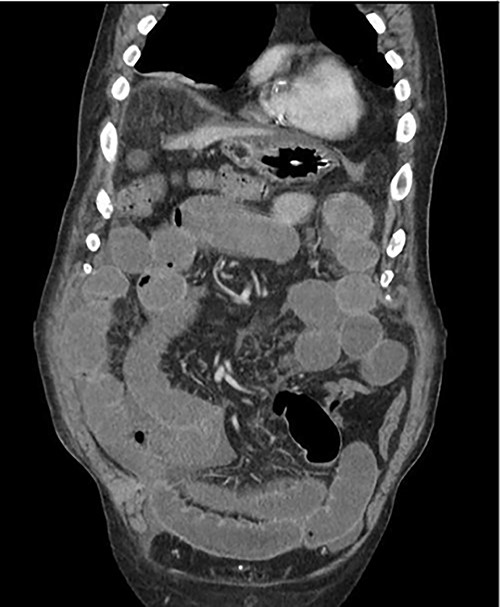

An 81-year-old male with past medical history of coronary artery disease, peripheral arterial disease, hypertension, dyslipidemia, hypothyroidism, benign prostatic hyperplasia, osteoarthritis, sleep apnea, gout and 10-pack year smoking history presented with complaints of abdominal distention and bloating. Patient had been suffering from recurrent bouts of constipation for ~2 weeks with last bowel movement noted to be over 2 days prior to presentation. Patient also complained of numerous episodes of nonbilious non-bloody vomiting. Abdominal computed tomography (CT) scan (Fig. 1) presented findings of a small bowel obstruction with transition point at the level of the terminal ileum. Notably, patient was also positive for coronavirus disease 2019 (COVID-19) infection. General surgery was consulted, and patient was initially treated with non-operative management with nasogastric tube and serial abdominal exams. However, a repeat abdominal CT scan (Fig. 2) after 6 days of attempted conservative management showed persistent diffuse small bowel distention and increased ascites. This combined with the fact that the patient had no prior colonoscopies or abdominal surgeries prompted surgical exploration. Patient underwent exploratory laparotomy; intraoperatively, he was found to have a palpable mass at the terminal ileum. A right hemicolectomy with a side-to-side functional end-to-end ileocolonic primary anastomosis was performed. Final pathology revealed diffuse peritoneal malignant mesothelioma with no nodal involvement and negative margins.